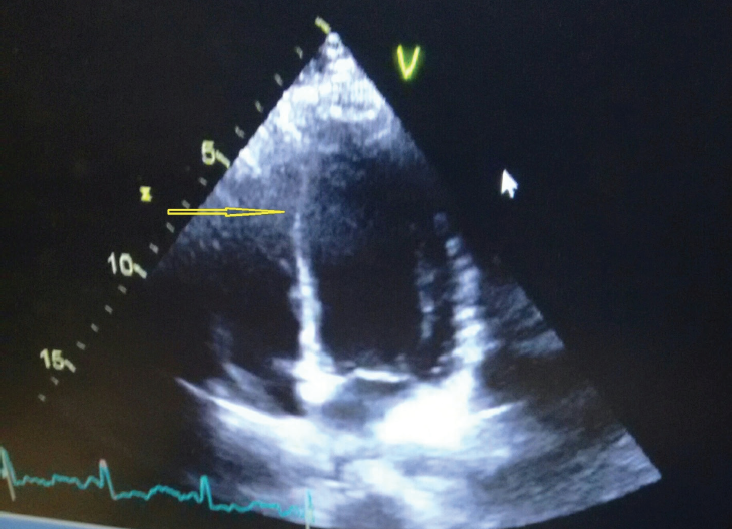

A 20-year-old woman presented for her first prenatal care visit at 32 weeks of gestation. Her pregnancy had been uneventful. An initial fetal ultrasonogram demonstrated an enlarged heart and aortic...

A 47‑year‑old woman presented with dyspnea, which she noted when she was playing with her children outside. Can you make a diagnosis?